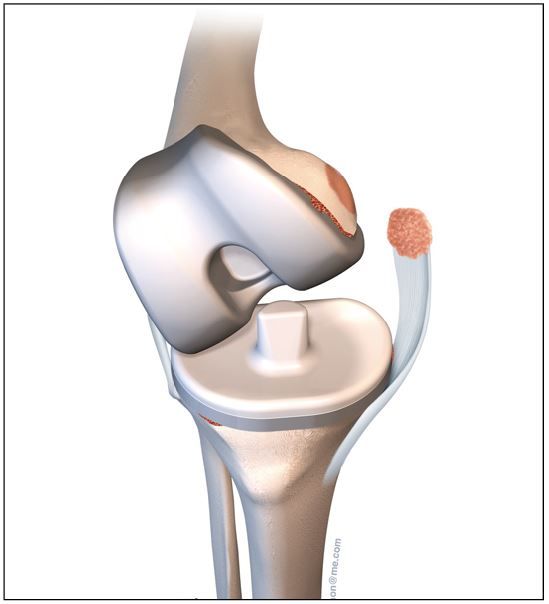

The risk of vascular injury and the difficulty of exposure is less when the femur is subluxated anterior, however, this situation is not without difficulties itself. Usually anterior subluxation of the femur on the tibia results in a significant flexion contracture and significant distal femur resection is needed to allow full extension of the knee and balance flexion and extension space. Based on my personal experience I strongly favor a hinge implant for posttraumatic anterior or posterior dislocations of the femur (Figure 5a, b, c, d).

My rational for this implant choice is that in severe anterior dislocation of the femur, often, the insertion of the collateral ligaments gets compromised when additional distal femur resection is needed to allow full extension. In addition, it is difficult to achieve reliable postoperative range of motion when encountering a knee subluxation in the presence of preoperative stiffness (less than 80 degrees arc of motion). Since the combination of a traumatic dislocation is seldom associated with an addition extraarticular deformity stemmed hinge implants can usually be used without problems.

4. I favor hinge implants for patients with anterior and posterior knee dislocations and an overall arc of motion of less than 80 degrees.